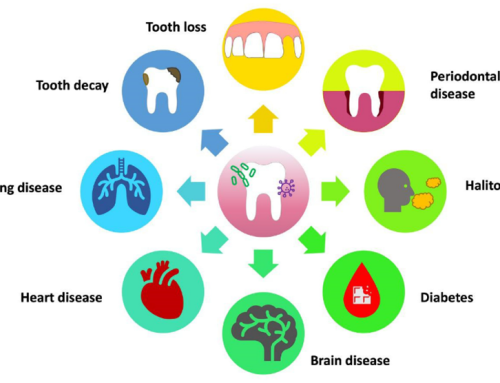

تحلیل لثه که اغلب به عنوان لثه های تحلیل رفته شناخته می شود، وضعیتی است که در آن بافت لثه اطراف دندان های شما شروع به عقب رفتن می کند و بخش بیشتری از دندان یا حتی ریشه آن را نمایان می سازد. تحلیل لثه اگرچه در ابتدا ممکن است یک مشکل زیبایی به نظر برسد، اما می تواند منجر به بروز مشکلات جدی سلامت دهان و دندان، از جمله افزایش حساسیت، افزایش خطر پوسیدگی دندان و حتی از دست دادن دندان در صورت عدم درمان شود.

برخلاف تصور رایج، تحلیل لثه فقط یک نگرانی زیبایی نیست. در حالی که ظاهر “دندان بلند” ناشی از آن ممکن است بر زیبایی لبخند شما تأثیر بگذارد، یک مشکل عملکردی قابل توجه نیز هست. نمایان بودن ریشه های دندان می تواند منجر به افزایش حساسیت، افزایش خطر پوسیدگی و در صورت عدم درمان، بی ثباتی یا از دست دادن دندان شود.

- بیماری لثه: تحلیل لثه تا حد زیادی ناشی از اختلالات پریودنتال از جمله ژنژیویت و پریودنتیت است. بافت لثه و استخوان زیر دندان های شما توسط این بیماری ها آسیب می بینند.

تحلیل لثه می تواند به عنوان یک مشکل جزئی شروع شود، اما اگر به آن رسیدگی نشود، می تواند منجر به بروز مشکلات قابل توجه سلامت دهان و دندان مانند حساسیت دندان، پوسیدگی و حتی از دست دادن دندان شود. شناسایی زود هنگام علائم و مراجعه به موقع برای درمان می تواند از آسیب بیشتر جلوگیری کرده و سلامت لثه شما را بازیابی کند.